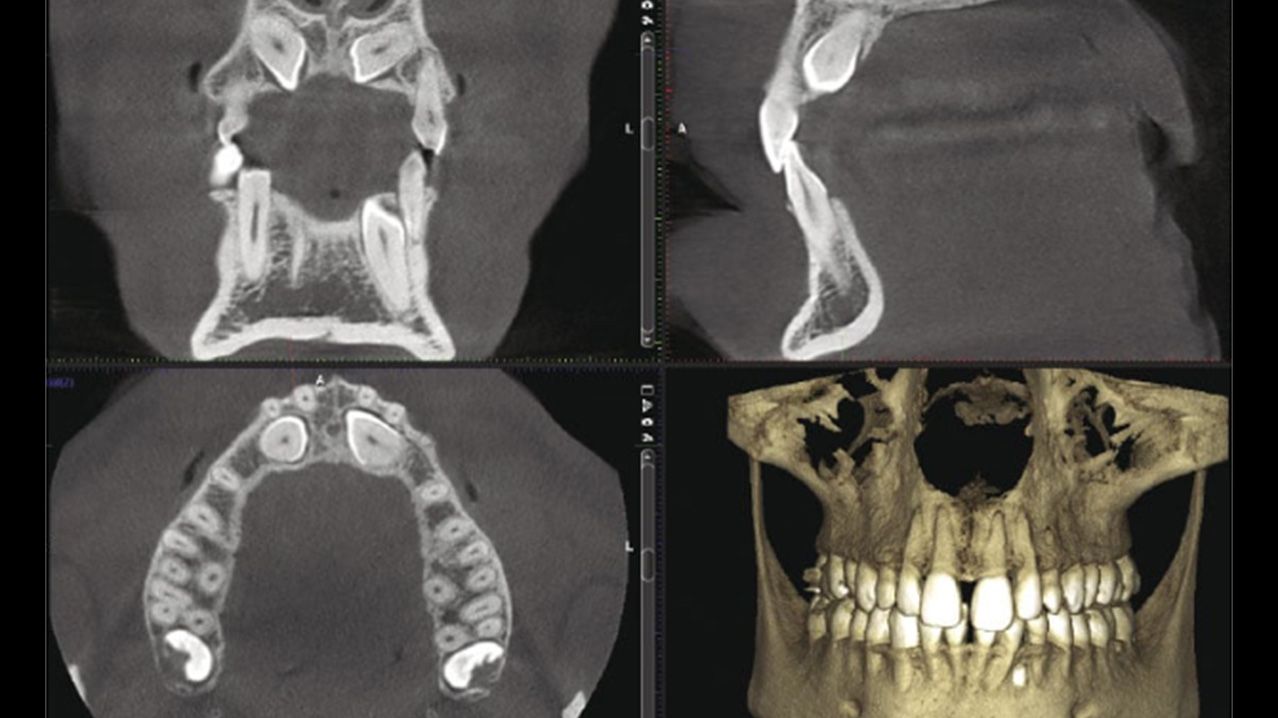

mosaïque de quatre visuels qui montrent des radiographies dentaires.

Numérique : Cone beam et Empreinte optique